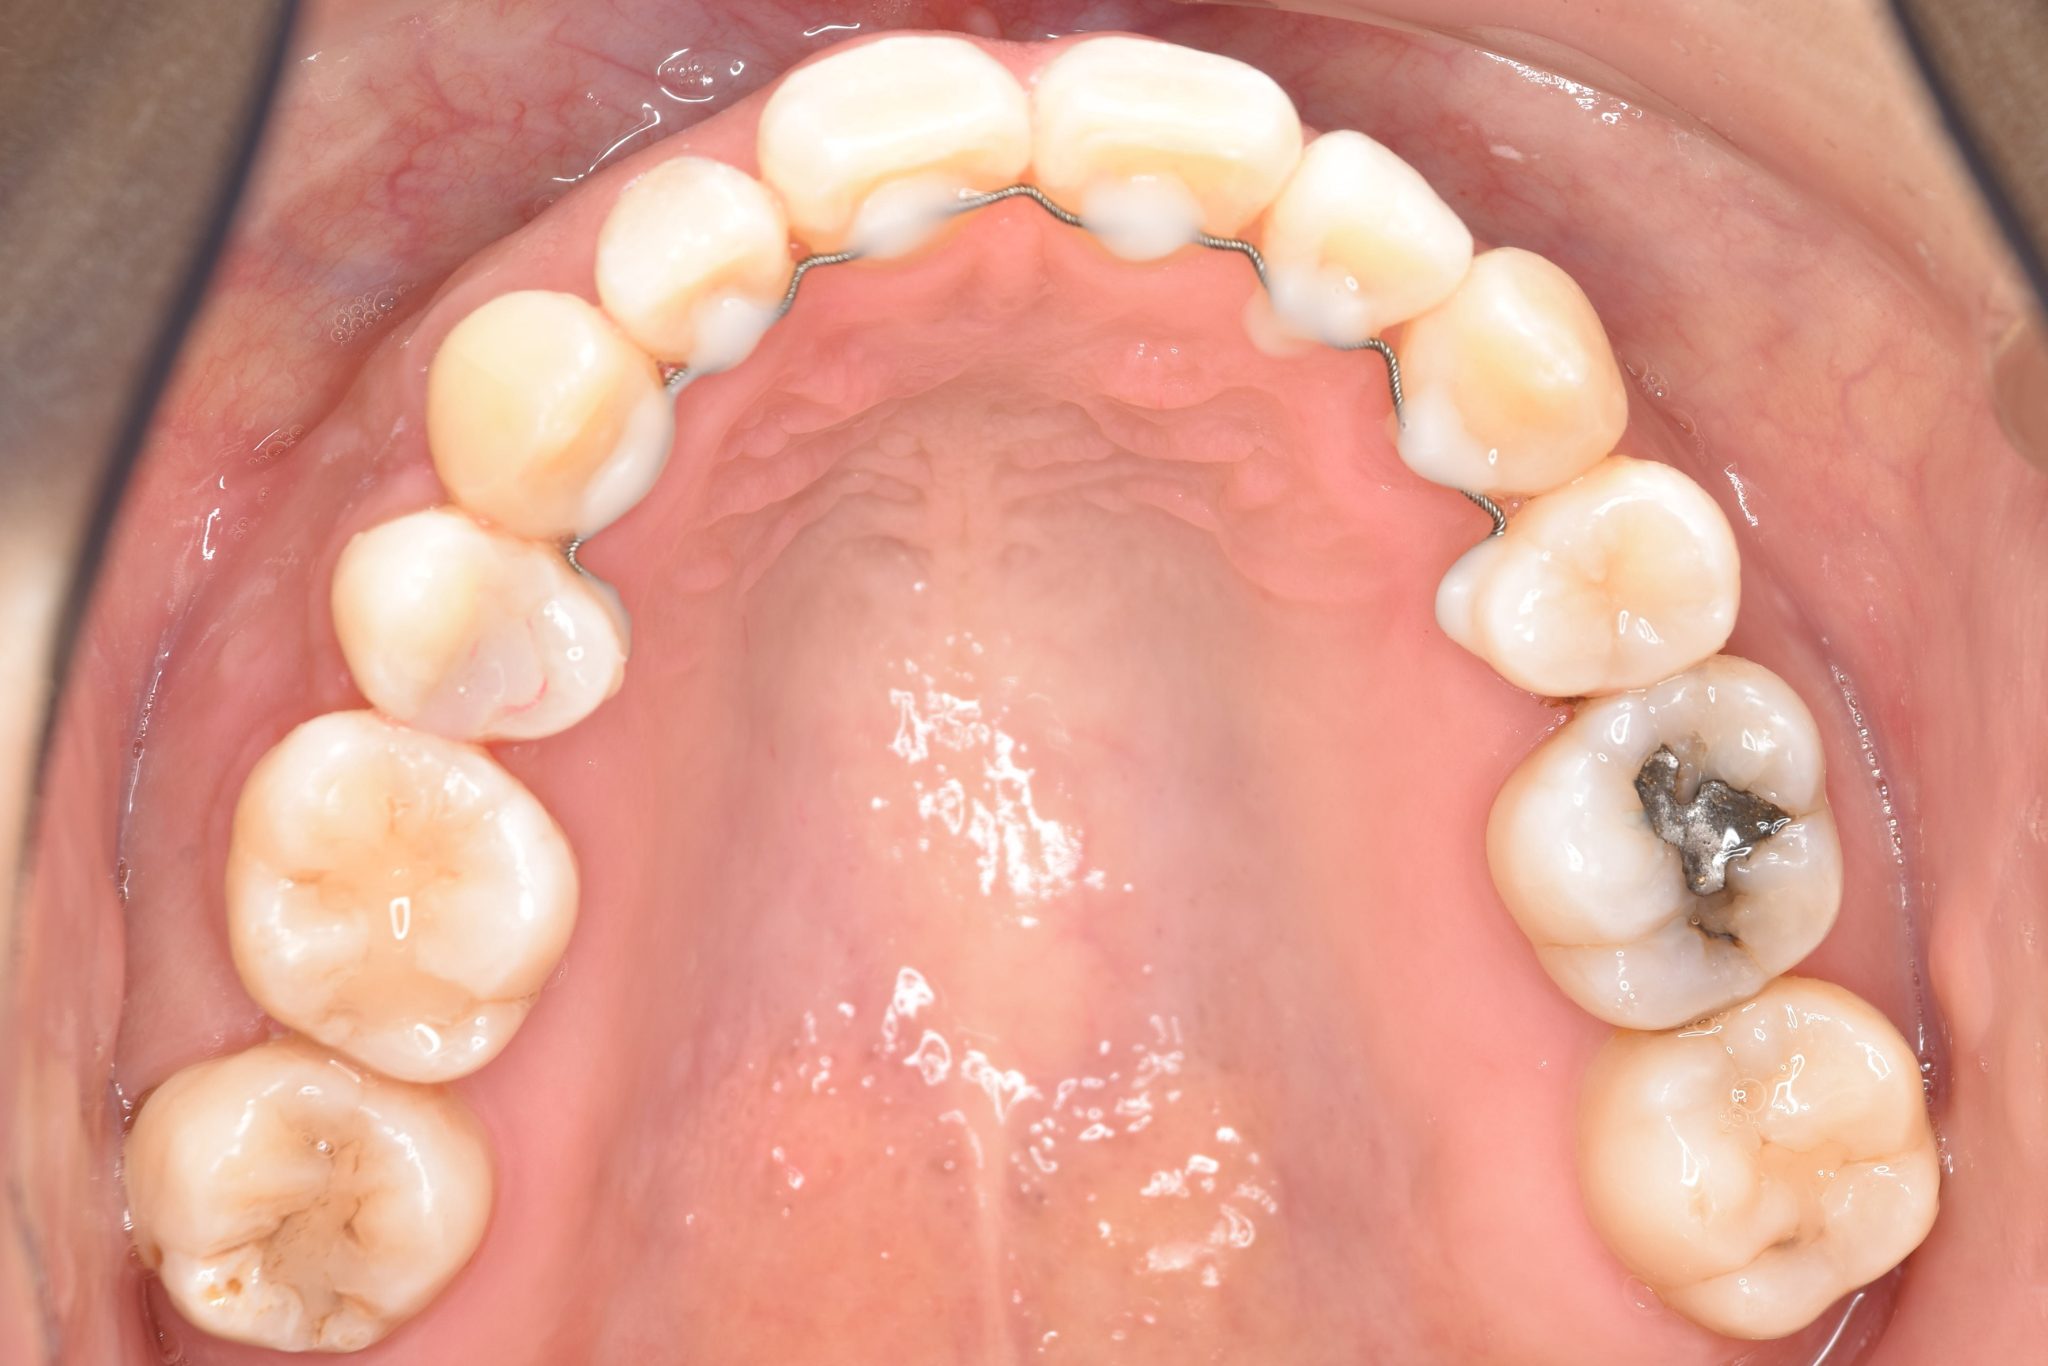

全顎ワイヤー矯正 症例_141